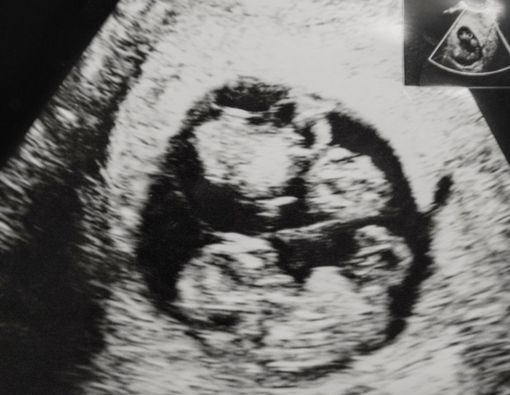

Kehamilan kembar dipercaya memiliki beberapa ciri-ciri tertentu yang dirasakan ibu hamil. Namun, hal tersebut tetap perlu dipastikan oleh pemeriksaan ultrasonografi (USG).

Mengapa USG sangat penting dalam kehamilan kembar? Pemeriksaan ini bertujuan untuk melihat kondisi janin di kandungan dan memastikannya dalam keadaan sehat.

Pemeriksaan USG bisa dilakukan di usia kandungan 5 minggu. Namun, pada masa ini biasanya hanya terlihat kantung kehamilan. Untuk memastikannya, Anda bisa melakukan USG kembali pada kandungan 8 minggu atau seterusnya.

2. Janin Kembar Berbagi Kantung Ketuban

Menurut dr. Arina, pemeriksaan hamil kembar tidak terdeteksi oleh USG bisa juga disebabkan karena dua bayi berbagi satu ketuban. Biasanya, kehamilan anak kembar mengembangkan kantung ketuban masing-masing.

Tetapi, beberapa kondisi memungkinkan hamil kembar hanya memiliki satu kantung ketuban. Hal inilah yang meningkatkan kemungkinan satu janin bersembunyi saat USG awal. Kondisi kembar ini disebut juga monoamniotik atau monochorionic.